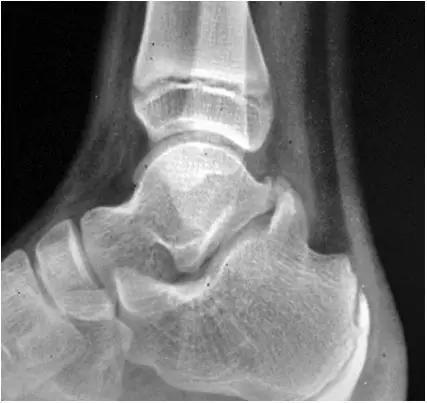

- 踝关节正侧位X 线平片,侧位片均显示距骨后方有三角形或椭圆形的距后三角骨。部分病例伴有轻度的踝关节骨性关节病。

三角籽骨综合征

三角籽骨综合征并跟腱滑囊积液